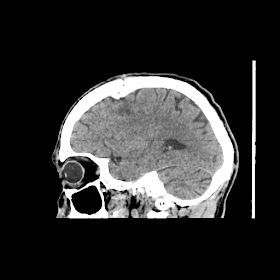

Radiologycal images :